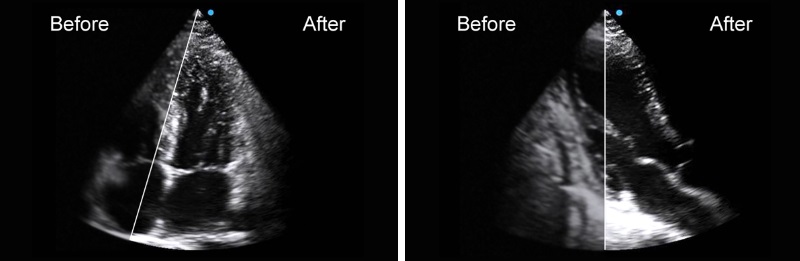

Crystal Purity Transducer

Equipped with the crystal purity transducer, Apogee 5800 Ace conducts superb scanning on cardiac diseases such as CHD (congenital heart disease).